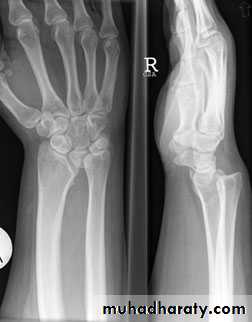

Madelung’s deformity

congenital or post-traumatic,the lower radius curves forwards (ventrally), carrying with it the carpus and hand but leaving the lower ulna sticking out as a lump on the back of the wrist.

The congenital

isolated entity

part of a generalized dysplasia;

although the abnormality is Present at birth but is rarely seen before the age of 10 years.

Function is usually excellent.

Treatment: If deformity is severe, the lower end of the ulna may be shortened; this is sometimes combined with osteotomy of the radius